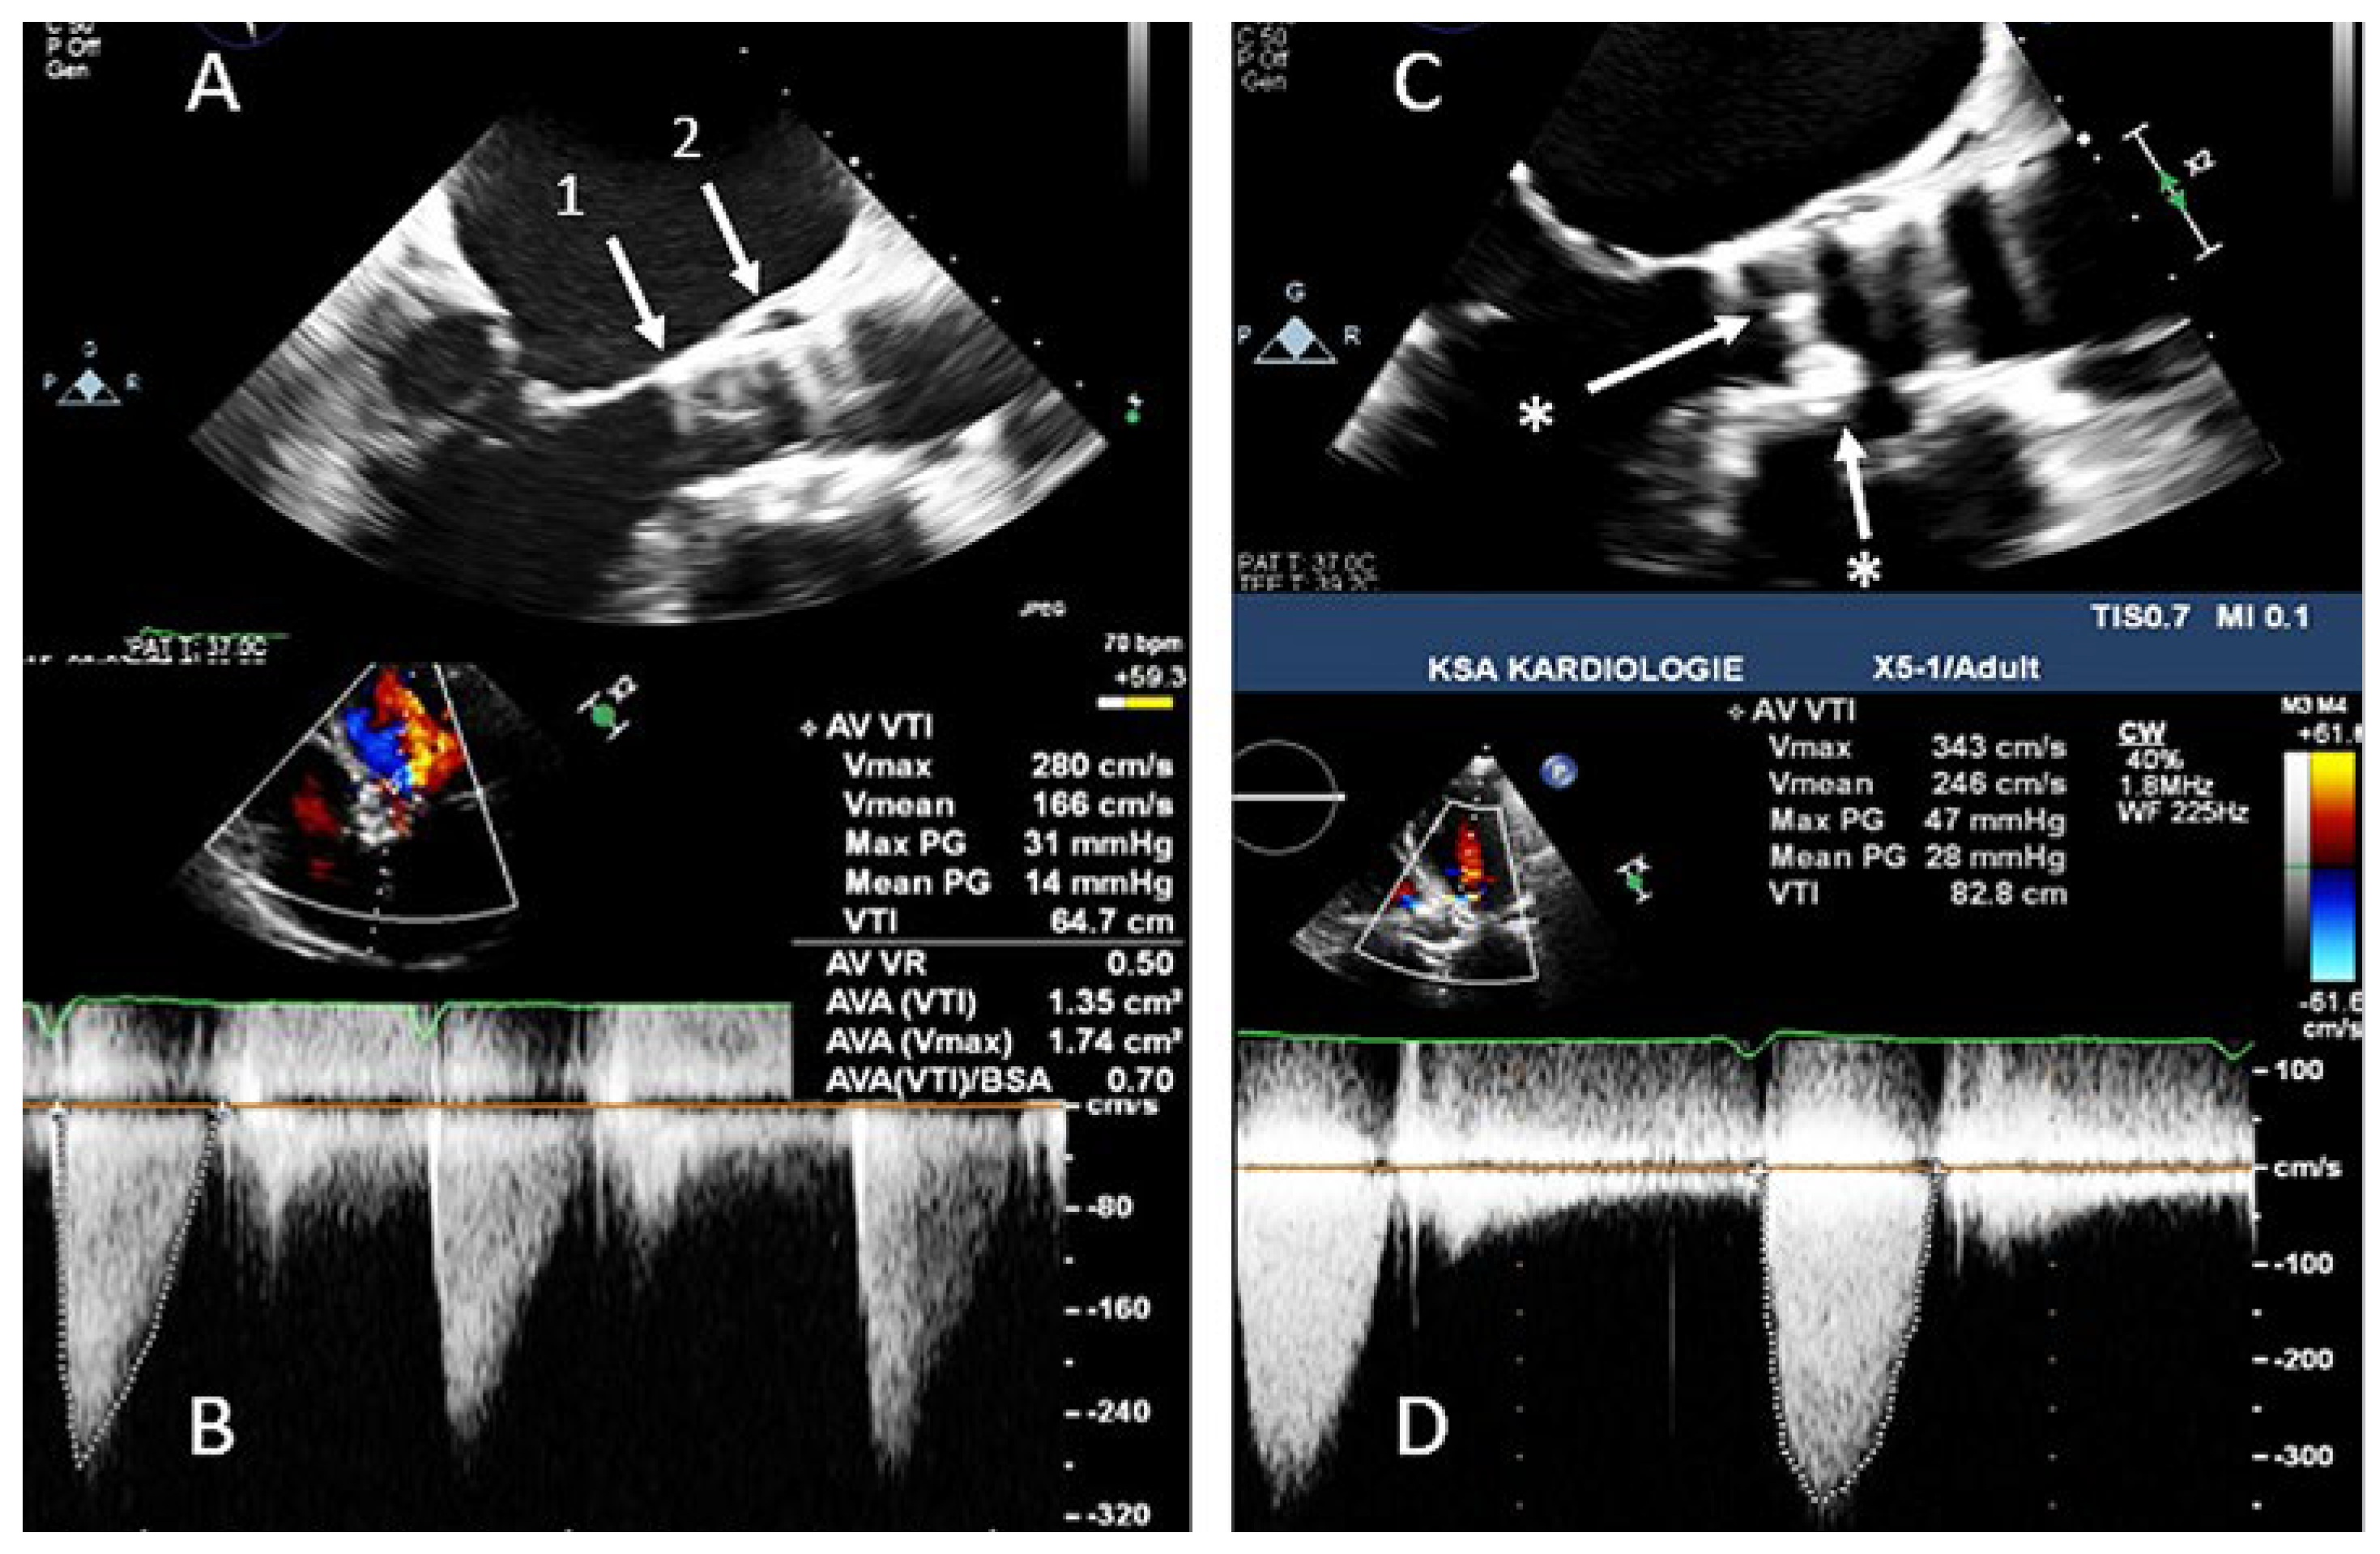

Thrombosis